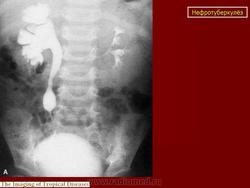

Рентгенологические методы исследования: флюорография (рентгенография) легких, обзорная и внутривенная урография в различных модификациях, томография почек, ретроградная пиелография, цистография, уретроцистопростатография, ангиография и др. Обзорный снимок мочевых путей позволяет обнаружить обызвествления в органах мочеполовой и других систем, изменения опорно-двигательного аппарата (туберкулезный спондилит, метастазы при раке почки и т. п.), определить контуры и размеры почек (увеличение или уменьшение, выбухания, втяжения). По внутривенной урограмме оцениваются функциональное состояние почек и анатомические особенности чашечно-лоханочной системы, мочеточников, мочевого пузыря; урография - основной рентгенологический метод исследования. Соответственно форме и стадии нефротуберкулеза могут быть выявлены; при субклиническом нефротуберкулезе - слабое контрастирование чашечно-лоханочной системы, хаотичное расположение чашечек, их деформация, при папиллите («начальном» деструктивном нефротуберкулезе) - неровность, стушеванность, нечеткость контуров чашечки ввиду наличия признака деструкции, при кавернозном туберкулезе - наличие полостей как в корковом, так и в мозговом слое с неровными, фестончатыми краями; при туберкулезном пионефрозе - изображение увеличенной почки с выбухающими неровными контурами, наличием больших полостей распада, нередко сливающихся между собой, резким снижением либо потерей функции (выключение - аутонефрэктомия); при нефросклерозе (вторично-сморщенная почка) - почка небольших размеров.

Начальный признак специфического поражения мочевых путей - расширение чашечно-лоханочной системы и мочеточника (снижение их сократительной способности в результате токсического воздействия, изменения функционального характера). Во всех случаях «неясной» уретерогидронефротической трансформации врач должен предположить наличие туберкулеза мочевой системы. В дальнейшем обнаруживают различные деформации чашечно-лоханочной системы (с уменьшением ее емкости) с явлениями гидрокаликоза; сужения мочеточника с расширением его выше стеноза; натянутость, четкообразную форму мочеточника; симптом подтянутости стенки мочевого пузыря; уменьшение емкости и различные деформации его контуров вплоть до появления двойного контура - симптома «песочных часов». При восходящей или микционной цистографии, урет-роцистопростатографии выявляют пузырно-мочеточниковый рефлюкс, а при последней - сужения уретры и затекание контрастного вещества в полости предстательной железы. Томографию почек применяют для уточнения контуров почки. Ретроградную пиелографию выполняют при неинформативности внутривенной урографии и для выяснения характера выключения туберкулезного очага (сопоставление пиело- и урографических данных). Ангиография позволяет получить представление об ангиоархитектонике пораженной почки, что важно при определении хирургической тактики.